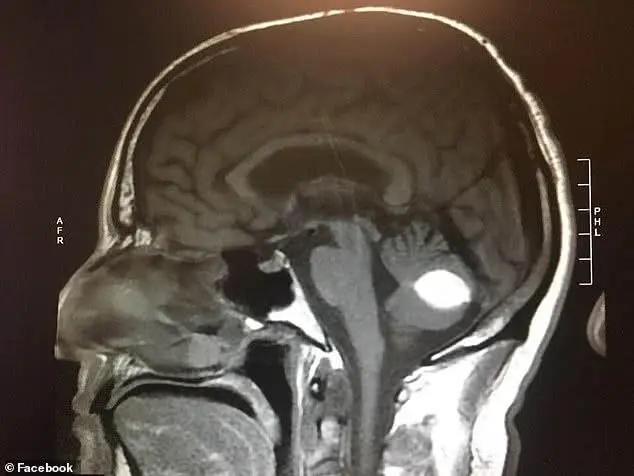

几个月前,伍德先生时常头痛欲裂,病发时不得不扶着墙壁走路。于是,他去医院做了检查。医生们给出了不同的诊断结果:一名加州大学旧金山分校的神经外科医生认为他患有颅内出血;另一名放射科医生认为他脑部有肿瘤。

然而,就在做手术的前一天,伍德先生被告知手术取消了。其原因是:术前的X光片显示,他的脑部已无任何异常。

没有接受任何的治疗而迅速恢复健康,医学专家们也对此感到十分困惑。理查德·绮博士说,“我们有做测试,也有相关的医疗技术,我们试图得出一些结论。但是,有时我们仍无法解释某些现象。”